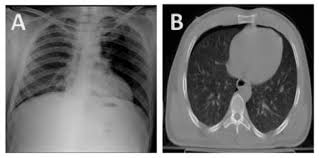

Pneumothorax High Res Stock Images Shutterstock from image.shutterstock.com Aug 11, 2021 · fenton 2013 growth calculator for preterm infants. The degree of collapse determines the clinical presentation of pneumothorax. Search only for pneumothorax x ray This buildup of air puts pressure on the lung, so it cannot expand Now with integrated gestational age calculator and decision support (e.g., retinopathy of prematurity, rsv prophylaxis). Jul 02, 2021 · a collapsed lung occurs when air escapes from the lung. Nov 16, 2020 · a pneumothorax is defined as a collection of air outside the lung but within the pleural cavity. Air can enter the pleural space by two mechanisms, either.

The air accumulation can apply pressure on the lung and make it collapse. Search only for pneumothorax x ray It occurs when air accumulates between the parietal and visceral pleurae inside the chest. The degree of collapse determines the clinical presentation of pneumothorax. Nov 16, 2020 · a pneumothorax is defined as a collection of air outside the lung but within the pleural cavity. The air then fills the space outside of the lung, between the lung and chest wall. This buildup of air puts pressure on the lung, so it cannot expand Air can enter the pleural space by two mechanisms, either. Jul 02, 2021 · a collapsed lung occurs when air escapes from the lung. Aug 11, 2021 · fenton 2013 growth calculator for preterm infants. Now with integrated gestational age calculator and decision support (e.g., retinopathy of prematurity, rsv prophylaxis).